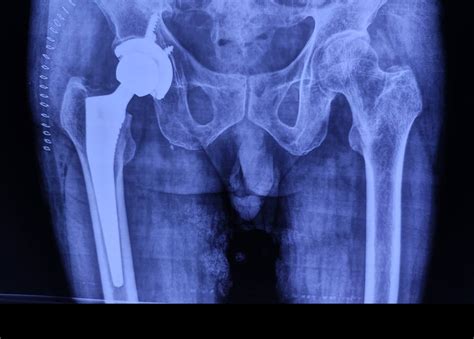

Conversely, if the fracture is severe or if the blood supply to the femoral head has been disrupted, a hip replacement may be necessary. In a partial hip replacement, only the head of the femur is replaced with a metal prosthesis. In a total hip replacement, both the head of the femur and the socket in the pelvic bone are replaced. This procedure is generally preferred for active older adults as it provides better long-term outcomes and reduces the risk of needing follow-up surgeries.

Partial Hip Replacement (Hemiarthroplasty) Femoral neck fractures Replaces only the femoral head with a metal prosthesis